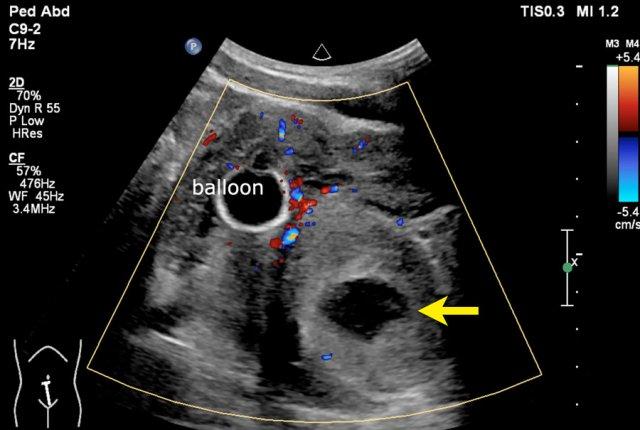

Example 2

Video về một bé gái ba tuổi có khối u lớn ở hông phải.

Siêu âm với đầu dò tần số cao cho thấy khối u xuất phát từ thận phải.

The remnant of the collecting system is dilated.

Same patient.

A tumor thrombus is present in the inferior caval vein.